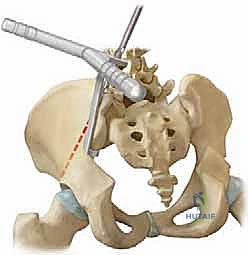

Distal fixation is arguably the most critical component of the construct, as failure to adequately control the pelvis will result in recurrent obliquity and sitting imbalance. The Galveston technique, or modern variations utilizing intra-iliac posts or screws, relies on the robust cortical bone between the inner and outer tables of the ilium. The optimal trajectory begins at the posterior superior iliac spine (PSIS) and advances anteriorly and distally, passing just superior to the greater sciatic notch. This trajectory maximizes bone purchase while avoiding the sciatic nerve and the superior gluteal neurovascular bundle. The surgeon must possess a pristine three-dimensional understanding of the pelvic anatomy, as the ilium in neuromuscular patients is often dysplastic, narrow, and severely rotated.

The foundation of the unit rod construct lies in the pelvis. The PSIS is identified, and a starting hole is created using a burr or awl. The trajectory is critical: the drill must pass between the inner and outer tables of the ilium, directed roughly 15 degrees laterally and 15 degrees caudally, aiming just superior to the sciatic notch.

A blunt probe is utilized to palpate the trajectory, ensuring there is no cortical breach into the sciatic notch or the true pelvis. Once the trajectory is confirmed, the pathway is sequentially enlarged to accommodate the distal limbs of the unit rod.